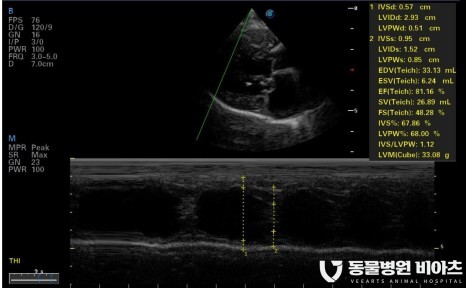

심장 초음파

심장 초음파는

심장 내강의 크기

심장벽 두께(LA:AO),

판막 모양의 이상 여부

혈관의 비정상적 확장 여부 등

엑스레이로는 확인이 어려운

심장 구조 변화의 많은 부분을 확인할 수 있습니다.